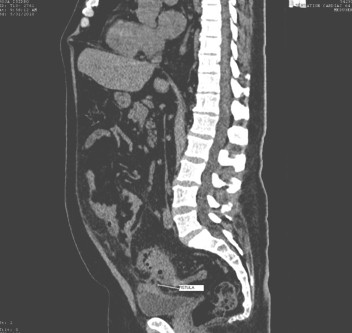

Se le realiza estudio tomográfico simple de abdomen y pelvis encontrándose los siguientes hallazgos: Lesiones néumicas en proyección del sigmoides y del colon descendente en relación con divertículos, con engrosamiento de la pared del sigmoides con una extensión de 13cm, distorsión de la grasa abdominal adyacente y presencia de trayecto fistuloso de 4cm del sigmoides a la vejiga existiendo discreta cantidad de aire en su interior